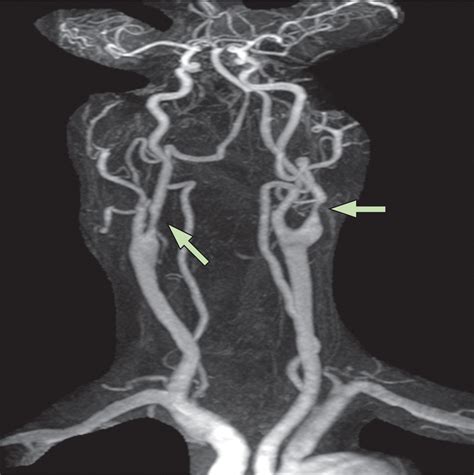

• Atherosclerosis: The buildup of plaque in the arteries, which can narrow the blood vessels and restrict blood flow.

• Carotid Artery Stenosis: Narrowing of the carotid arteries, often due to plaque buildup, which can increase the risk of stroke.

The results of a Carotid Artery Scan are typically interpreted by a radiologist or vascular specialist. The findings are usually categorized based on the degree of stenosis (narrowing) in the arteries:

Degree of Stenosis Interpretation

0-15% Normal or minimal plaque

16-49% Mild stenosis

50-69% Moderate stenosis

70-99% Severe stenosis

100% Complete occlusion

Based on the results, healthcare providers may recommend further testing, lifestyle changes, or medical interventions to manage the condition and reduce the risk of stroke.